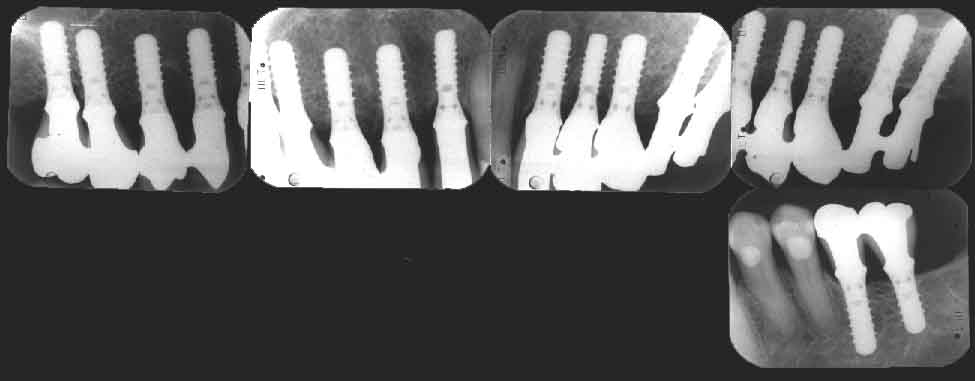

vue plus précise de ces implants mis en place depuis plus de cinq ans sur des radiographies intraorales